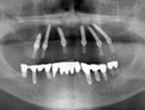

Case.02 オールオン4症例

初診時

上顎の残存歯を保存してインプラント治療を行った場合は、インプラント本数が多くなり、臼歯部への骨造成も必要となるため、しっかり噛めるようになるまでに約9ヶ月間かかります。患者さんが早期回復を要望されたため、残存歯を戦略的に抜歯してAll-on-4(オールオンフォー)による即日完了治療を選択しました。

(下顎のインプラント治療は他院で行われたものです)

レントゲン

正面

上顎

下顎